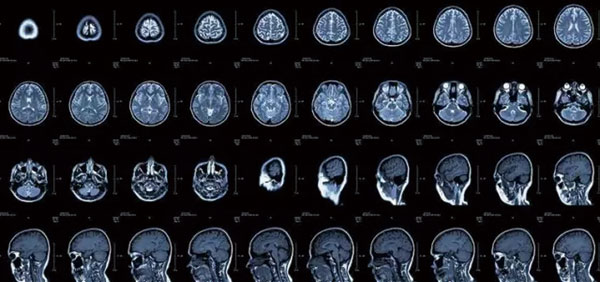

CT像把面包切片看

CT的检查原理是X线会分层穿过人体,之后通过电脑计算后二次成像,就像把一片面包切成片来看。优点是可以分层看,经计算后可以显示出更多的组织信息。

2、颈椎腰椎——最佳选核磁,次选CT

颈椎病、腰椎间盘突出等椎间盘疾病需要观察椎间盘与相应的神经根,要想更好观察这些软组织,最优选择就是核磁。同样,对于关节、肌肉、脂肪组织检查,核磁也是首选。

3、胸部——粗看X线片,细看CT,看肺不要选核磁

X线胸片可粗略检查心脏、主动脉、肺、胸膜、肋骨等,可以检查有无肺纹理增多、肺部钙化点、主动脉结钙化等。

胸部CT检查显示出的结构更清晰,对胸部病变检出敏感性和显示病变的准确性均优于常规X线胸片,特别是对于早期肺癌确诊有决定性意义。但是CT检查的辐射剂量高于X线。核磁对于肺部疾病的诊断,应用非常有限。